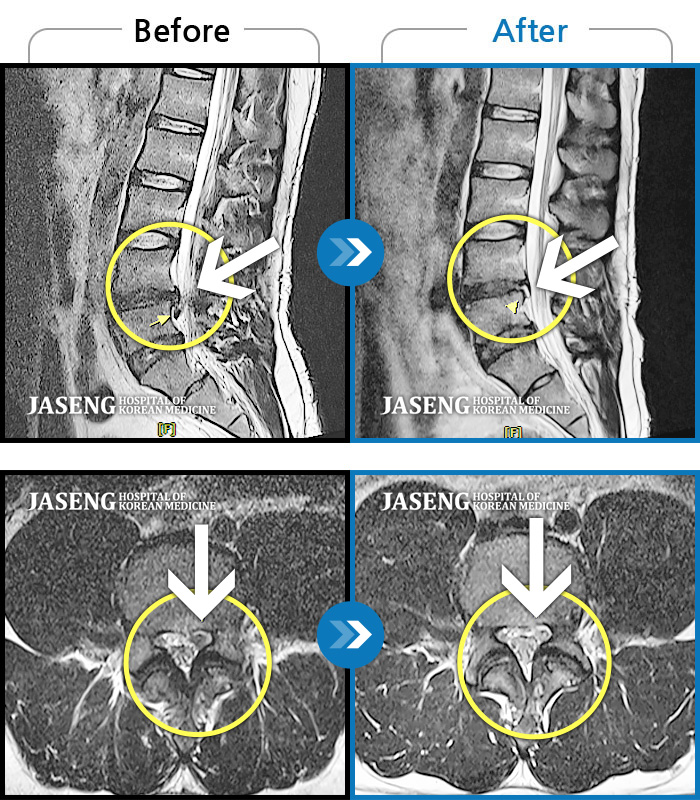

허리디스크

광주 · 이일석 원장

허리부터 골반이 묵직하고 뻐근한 통증, 우측 허벅지까지 이어지는 저림 증상으로 내원하셨습니다.

촬영시기

2025.01.20 ~ 2025.10.25

2025.10.30